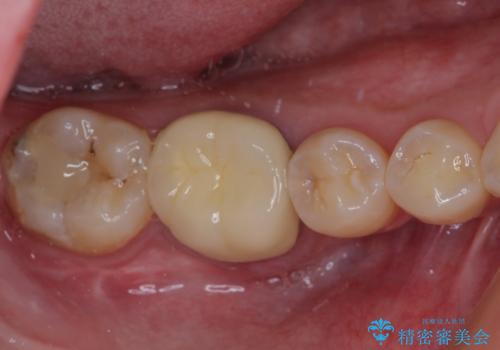

病変が消退しているかどうか、半年、1年とレントゲン写真で経過観察を行う必要があります。

海外に行かれていた都合で、術後2年での経過観察となりましたが、無事に病変の消失が認められました。